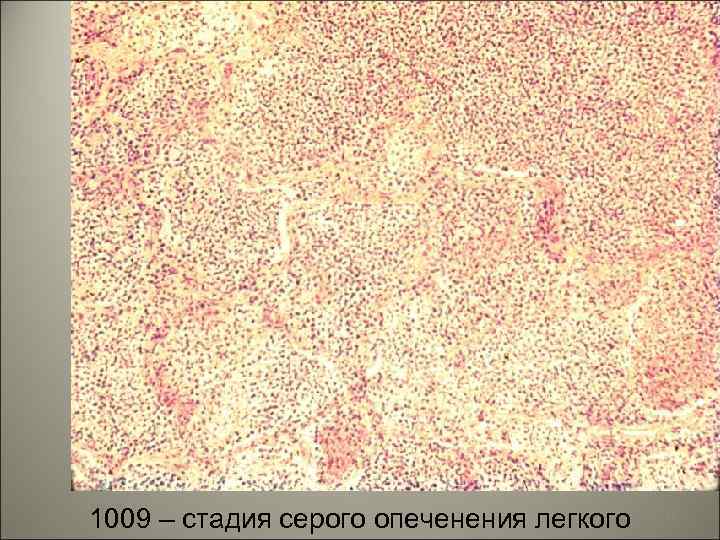

1225 – стадия красного опеченения легкого 50

• III. Стадия серого опеченения наблюдается на 4 -6 -й день болезни. В альвеолы выселяются макрофаги, захватывают гемоглобиногенные пигменты и постепенно их удаляют по лимфатическому руслу. Выселяется большое количество нейтрофильных лейкоцитов, происходит фибринолитическое воздействие нейтрофилов на выпавший фибрин. 51

1009 – стадия серого опеченения легкого 52

• Цвет легкого меняется - легкое становится серым. Пораженная доля легкого увеличивается в размере, плотная, тяжелая, на плевре значительные фибринозные наложения. Лимфатические узлы корня легкого увеличены. 53